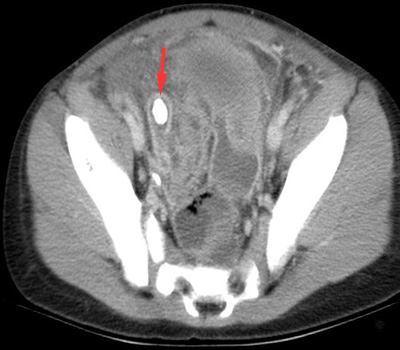

| US confirms a dilated appendix with the calcified appendicolith. | CT confirms the calcified appendicolith and findings of appendicitis. |